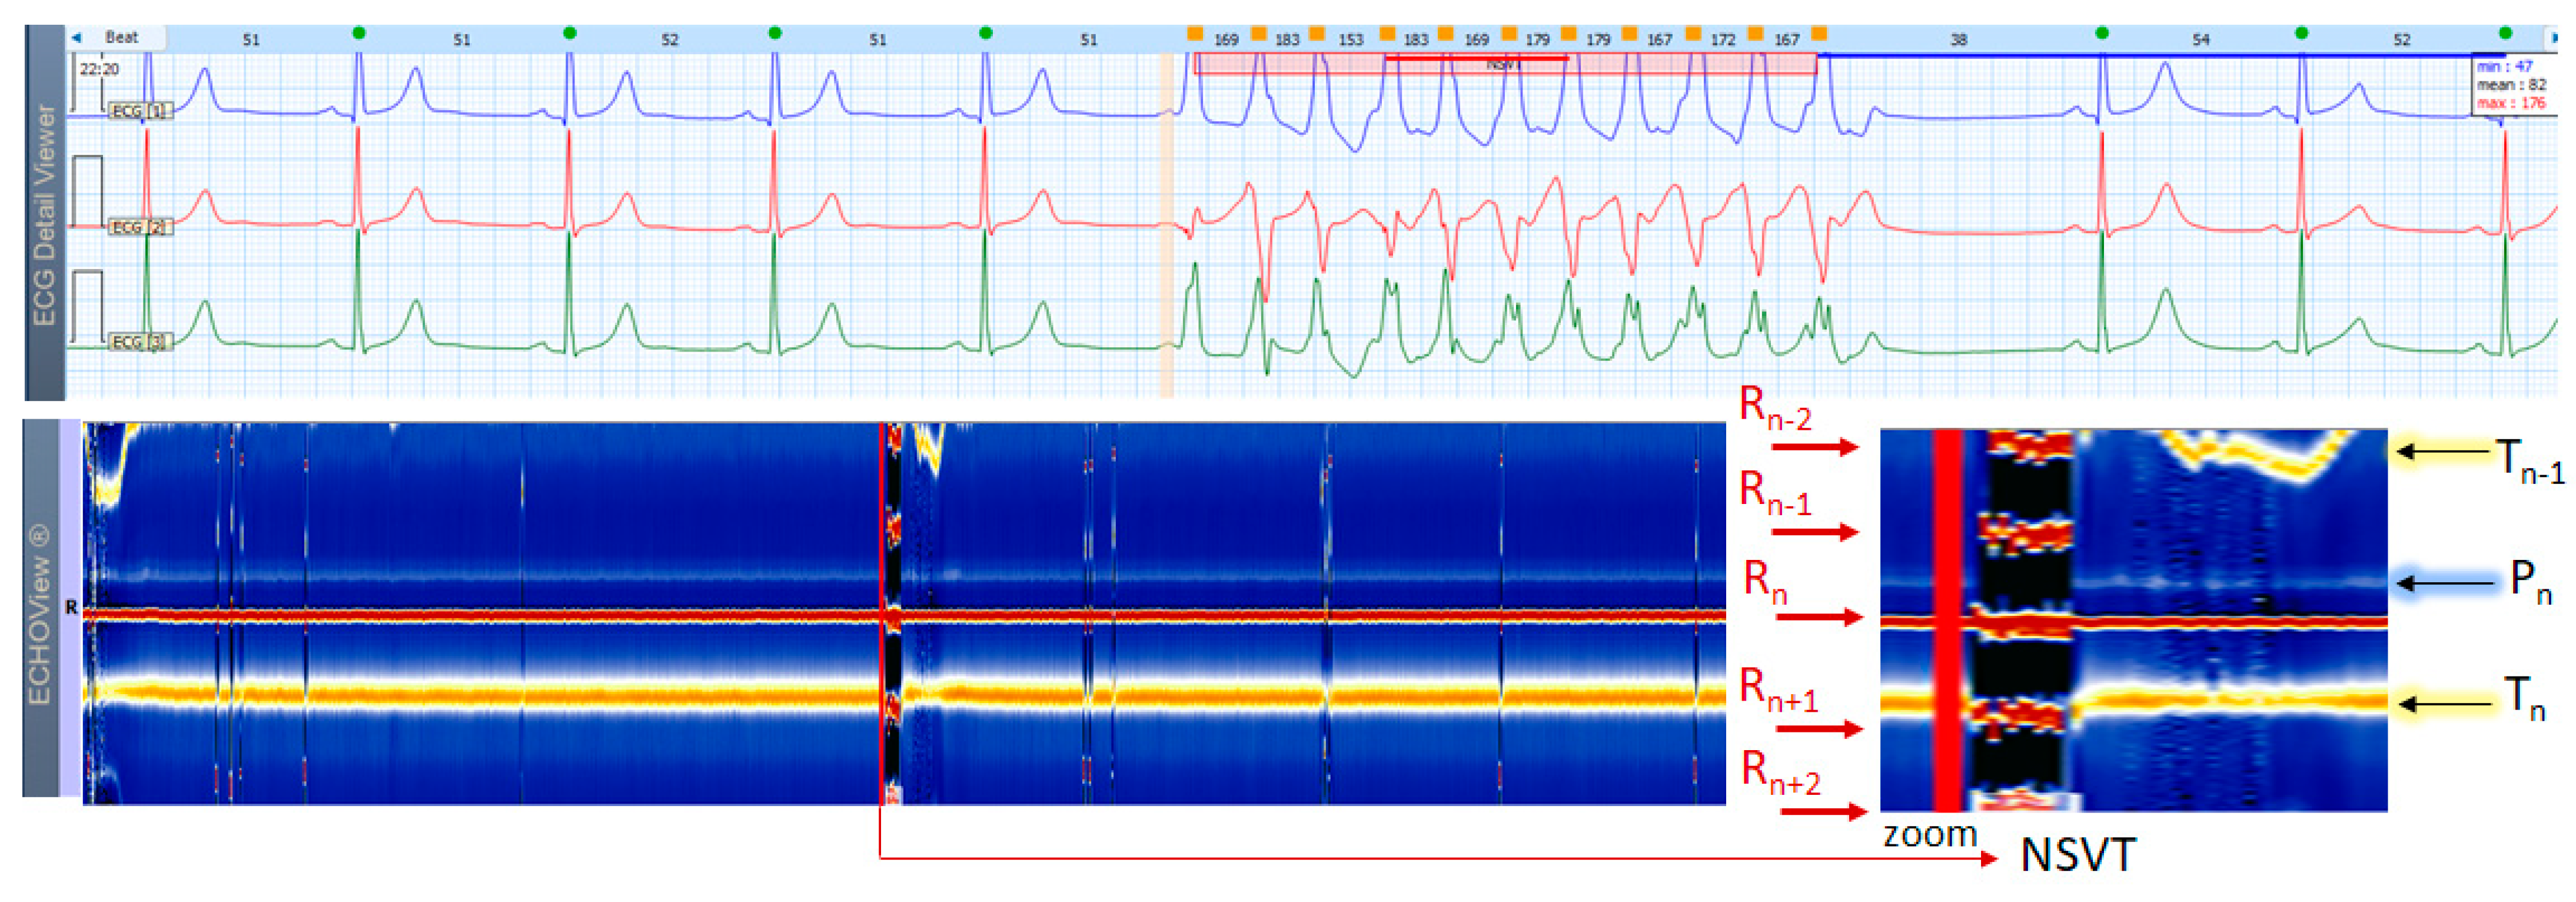

3.8. Ventricular Arrhythmia Case

The example in Figure 17 shows a Holter ECG strip and the corresponding ECHOView map, including a short rush of NSVT in a patient with NSR. NSVT is a broad-QRS complex tachycardia that is usually easily recognized in ECG strips. However, SVT in some patients with functional or fixed branch block could also be presented in ECG as a broad-QRS complex tachycardia, making differentiation from a VT difficult. In ECHOView, VT has a quite distinguishable pattern with red/black bands, corresponding to the strongly positive/negative R/T waves, respectively. The ventricular origin of this high-rate arrhythmia can be confirmed by different ECHOView observations, such as the absence of P-wave band due to the lack of normal atrial excitation; inversion of the color of the T-wave band due to ST-segment depression and inversion of the T-wave electric axis; appearance of several R-wave bands due to RR-interval shortening; widening of the central R-wave band due to QRS complex enlargement.

Although diagnosing VT may not be a major problem in ECG, reliably detecting typically brief episodes of NSTV in a 24-h Holter ECG is a challenge that compressed ECHOView images can greatly assist.

4.3. ECHOView: Summary of the Principles of Imaging